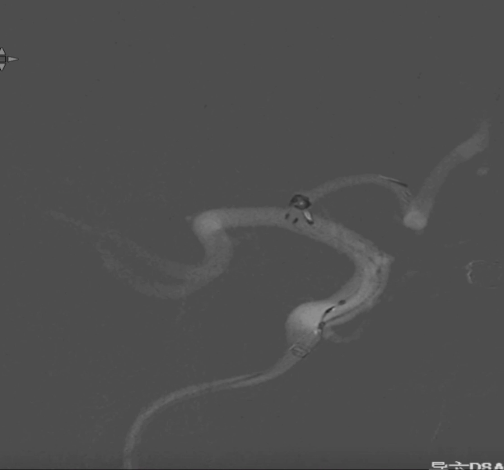

术前外院 DSA 2025-02

箭头所指右侧A1微小动脉瘤

现病史:患者于20天前行脑血管造影时发现右侧大脑前动脉A1起始部动脉瘤,偶有枕部酸胀感,无头晕、恶心、呕吐等,为行手术治疗来我院,门诊以"颅内动脉瘤"收入院。